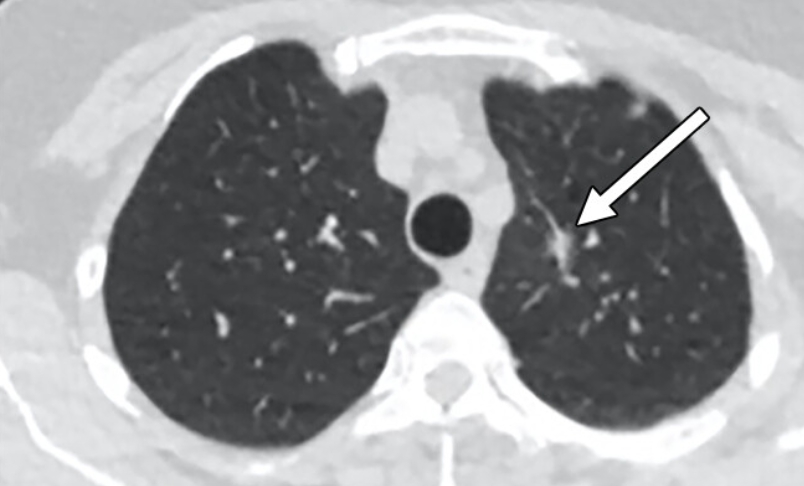

흉부ct로 볼수있는 질환 폐질환뿐 아니라 심장과 혈관, 흉막, 림프절, 뼈 구조까지 한 번에 보여줍니다. 폐렴, 결핵, 폐기종, 기관지확장증, 간질성 폐질환 같은 호흡기 질환은 기본이고, 폐에 생긴 작은 결절이나 혹도 세밀하게 확인할 수 있습니다. 폐암이나 전이암처럼 초기에 증상이 거의 없는 병은 CT로 발견되는 경우가 많아요.

흉부CT는 병이 있는지 없는지를 넘어서, 병의 진행 정도와 주변 장기 침범 여부까지 보여줍니다. 예를 들어 폐암의 경우, 5mm 미만의 아주 작은 결절까지 찾아내고, 종양이 혈관이나 기관지에 닿았는지도 확인합니다. 초기에 잡아내면 완치율이 크게 높아지죠.

또한 폐렴이 감염인지, 결핵성인지, 종양에 의한 것인지도 구분할 수 있습니다. 엑스레이에서는 그냥 ‘흐린 그림자’로만 보이던 것도, CT에서는 염증의 경계와 내부 구조까지 뚜렷하게 드러납니다.

| 감염성 질환 | 세균성 폐렴, 바이러스성 폐렴, 진균 감염 | 염증의 분포 형태로 감염 원인을 구분해 치료 방향을 결정합니다. |